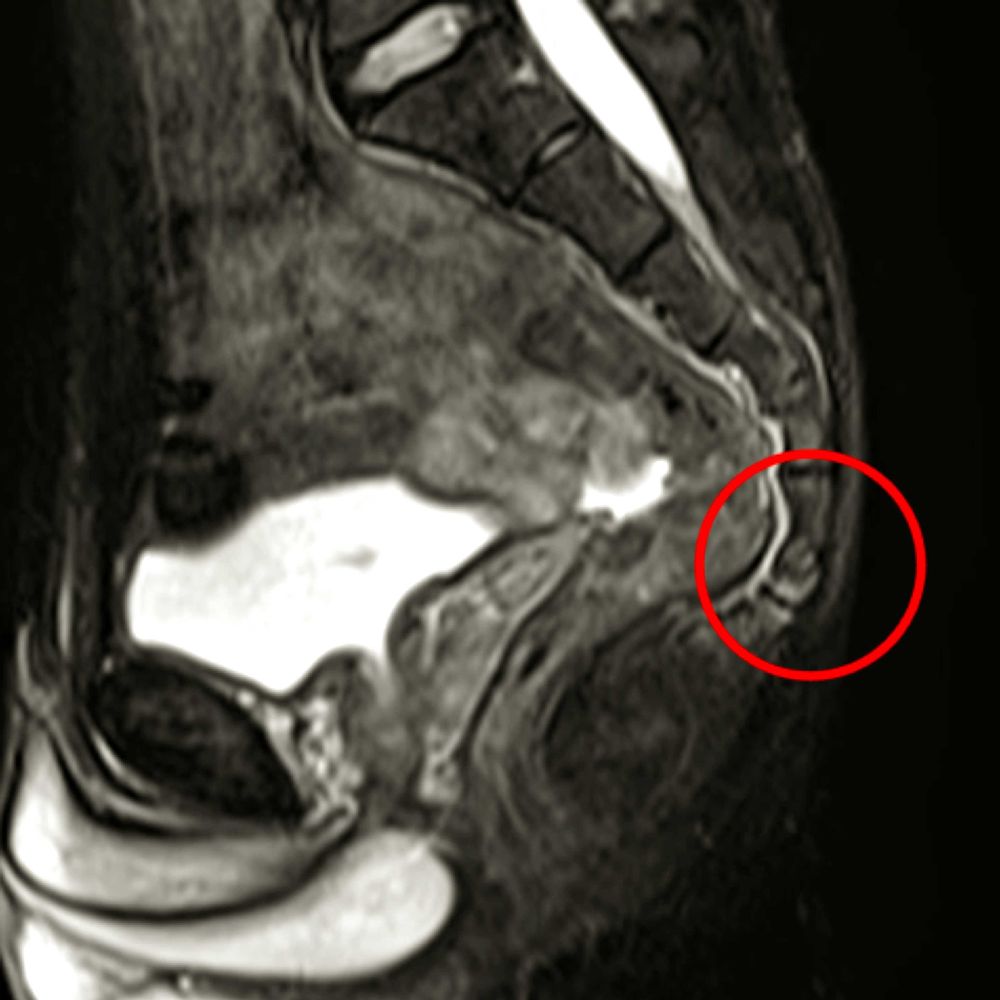

尾てい骨のレントゲン🫣